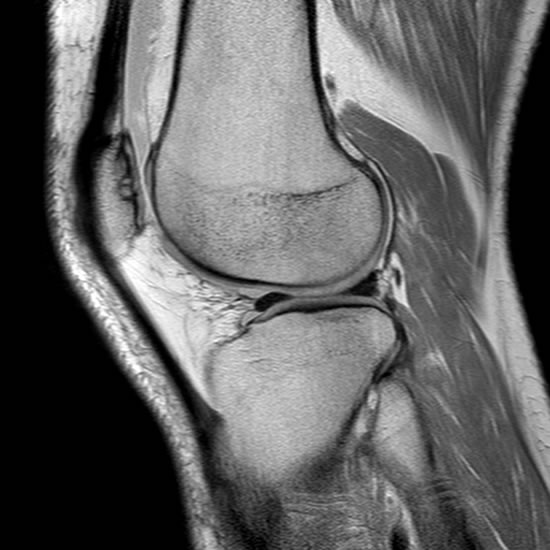

Resonancia Rodilla Te Meten Entera. WebResonancia magnética de la rodilla. Una IRM (imagen por resonancia magnética) de la rodilla utiliza energía de imanes potentes para crear imágenes de la articulación, músculos y tejidos de la rodilla. Una IRM no emplea radiación (rayos X). Las imágenes por IRM solas. .

Resonancia Magnética – Rodilla – Centro Médico Dr. Serván